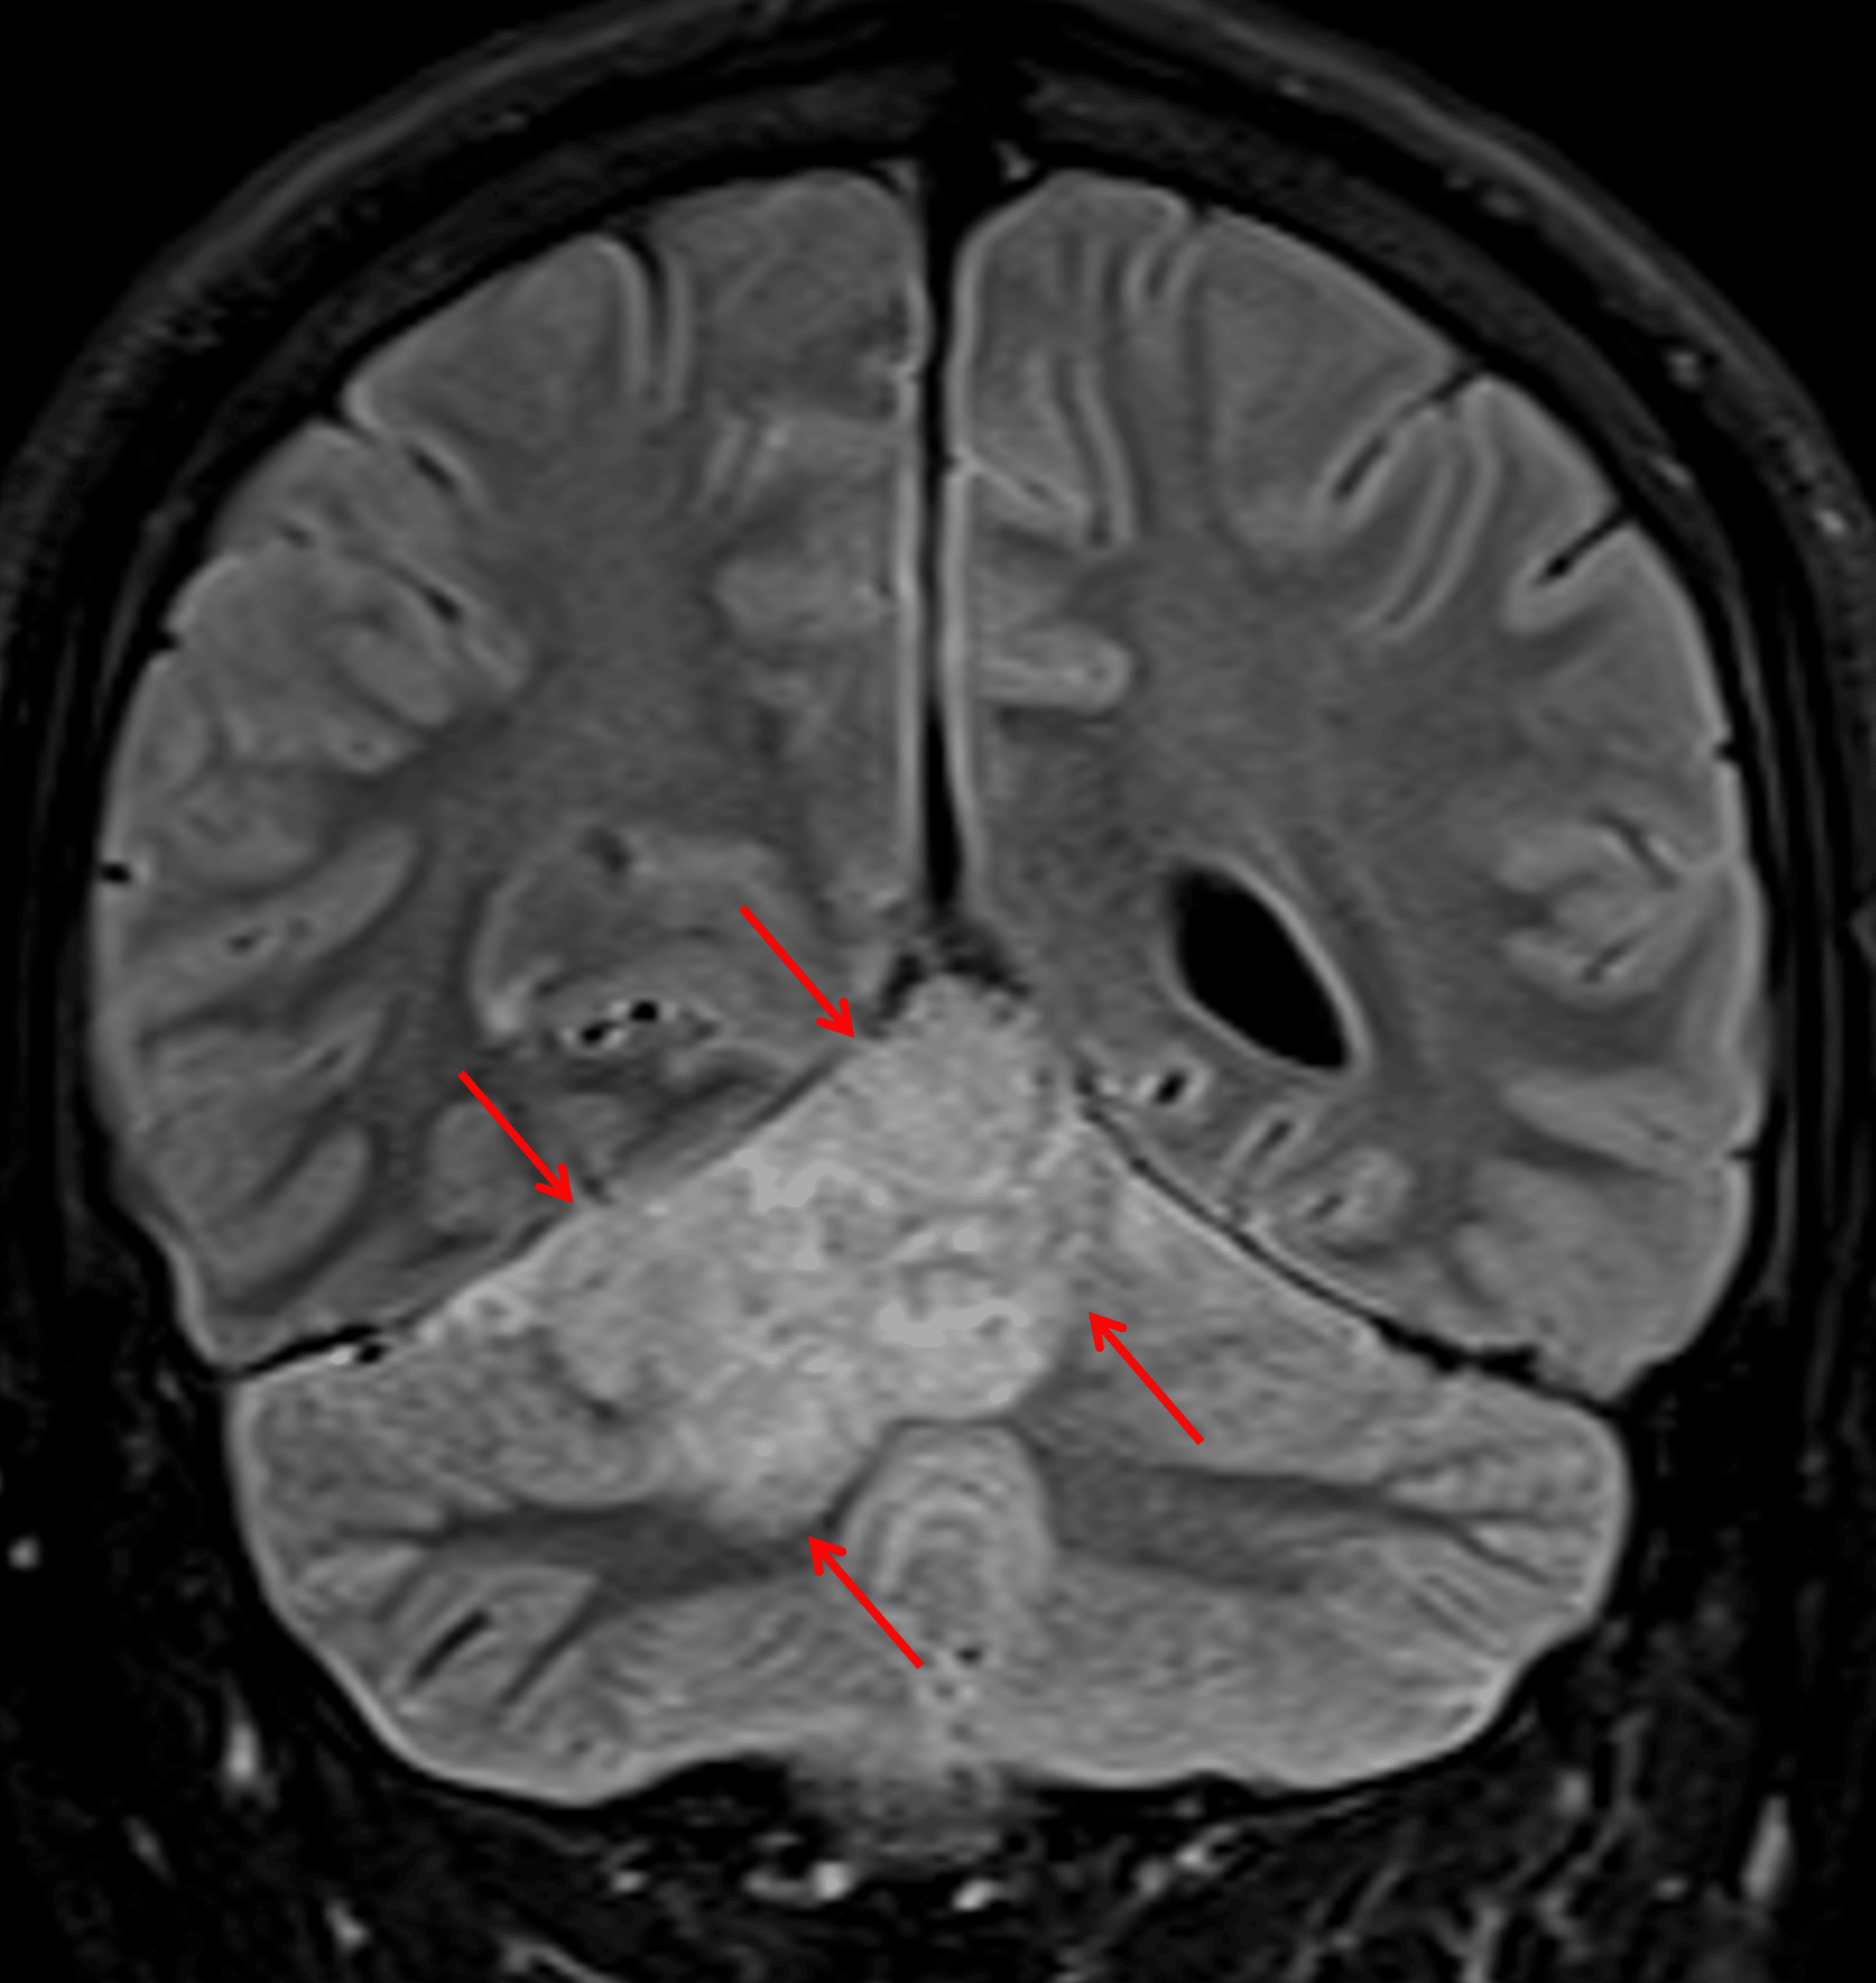

T2/FLAIR hyperintense mass in the superior aspect of the right cerebellar hemisphere and vermis (red arrows).